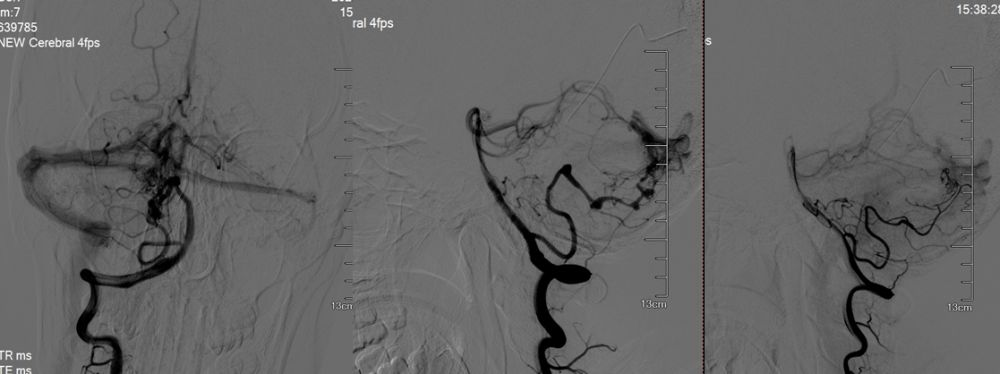

全麻满意后,常规消毒铺巾,采用改良 Seldinger技术穿刺右侧股动脉成功,置入6F动脉鞘黑泥鳅导丝带领5F造影导管行脑动脉造影可见右侧枕叶动静脉畸形团,血管畸形团由右侧PICA,右侧小脑上动脉及左侧PICA供血,右侧PICA多发动脉瘤。

图2 造影可见右侧枕叶、小脑动静脉畸形团,由右侧PICA、右侧小脑上及左侧PICA供血,且右侧PICA串珠样动脉瘤改变

图3 Synchro--14微导丝将 Headway17微导管超选进入远端动脉瘤中,送入数枚弹簧圈,后退微导管至近端动脉瘤后同样送入弹簧圈数枚,并闭塞载瘤动脉